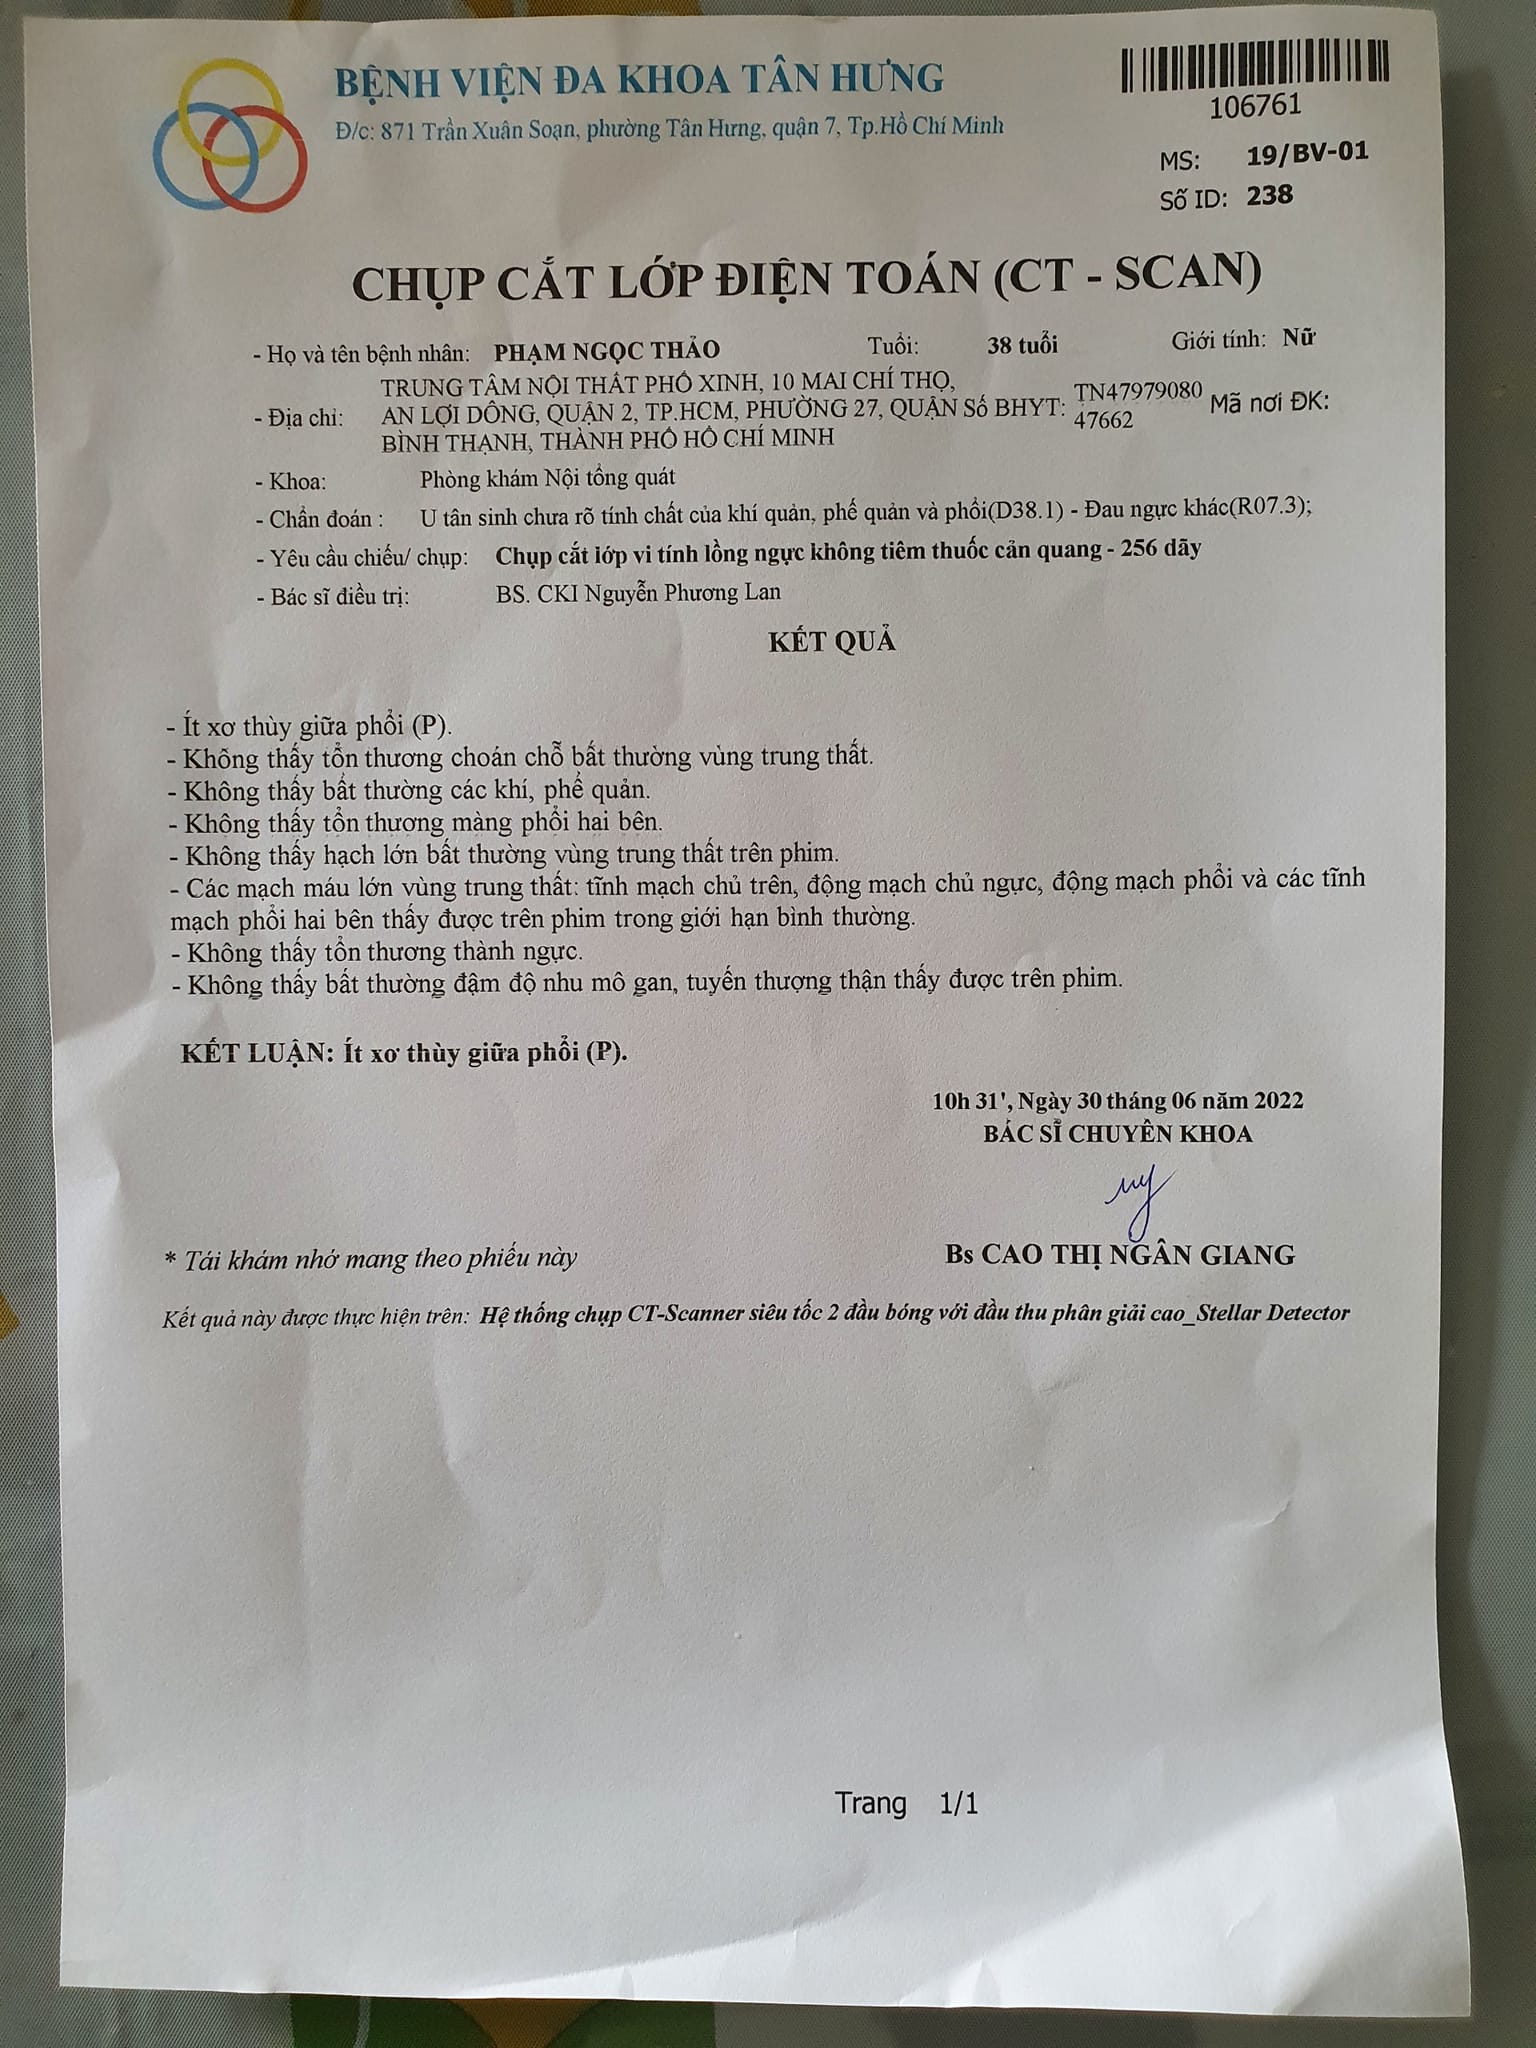

Kết quả X quang của bệnh nhân trước khi chăm sóc sức khỏe bằng Năng lượng sinh học vào ngày 26/11/2020

Kết quả X quang và CT sau khi chăm sóc sức khỏe bằng Năng lượng sinh học vào ngày 30/6/2022